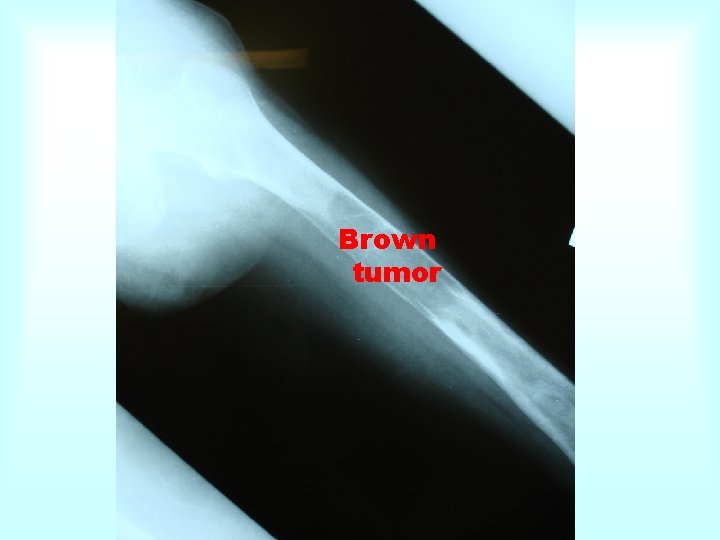

Brown tumor